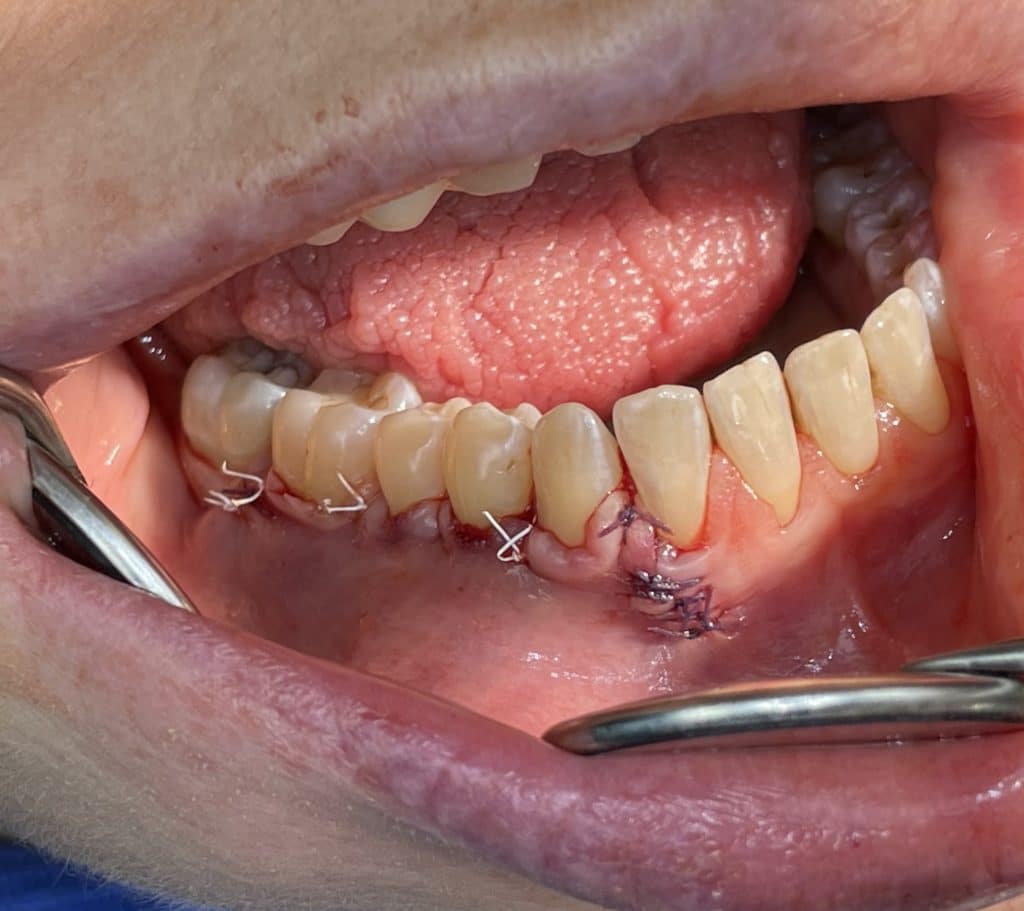

In quadrant 4, we initially proceeded with the reconstruction of the cervical part of the teeth and, where present, the removal of caries. Subsequently, we performed a bilaminar technique for multiple gingival recessions using a trapezoidal-shaped flap and minimal relieving incisions. We harvested a connective tissue graft from the palate, which was sutured to the periosteum and then covered with the coronally advanced flap, following the bilaminar technique. The sutures were removed after 10 days.

the suture of the covering flap in the multiple bilaminar technique